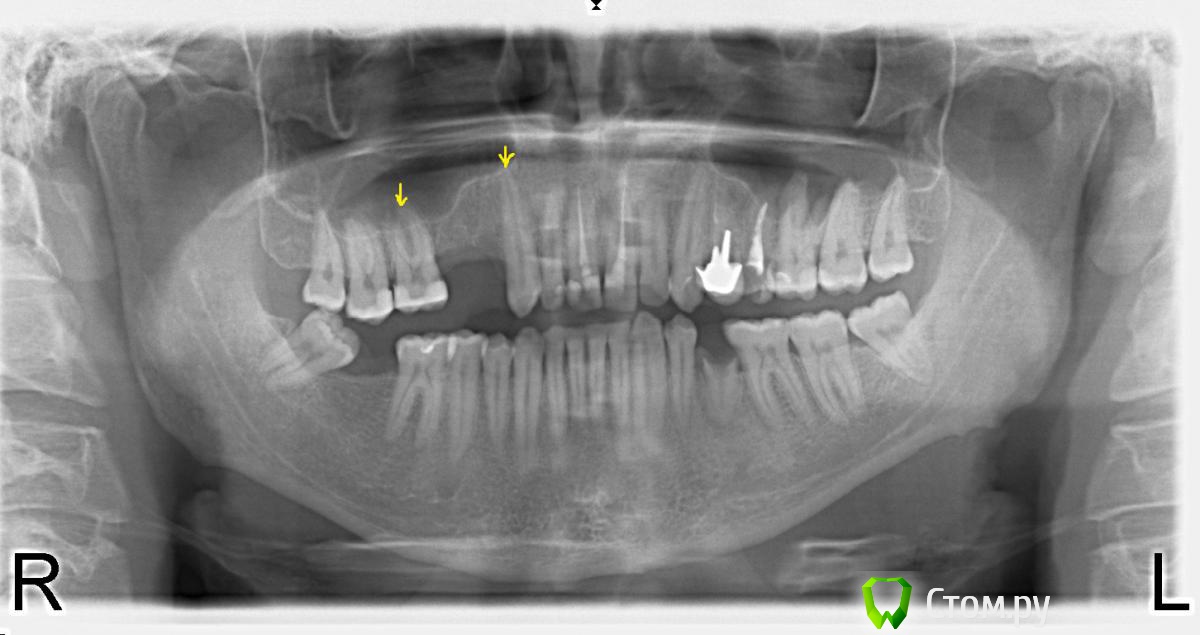

X555Y Опубликовано 16 декабря, 2013 Поделиться Опубликовано 16 декабря, 2013 Здравствуйте! Решил обратиться за советом на данный форум. История такая: отсутствуют справа сверху 4 и 5. Соответственно, необходимо заместить удаленные зубы на мост/импланты.«+» и «–» обоих видов протезирования понятны и известны. Основные минусы для меня:цена имплантации очень напрягает.. - порядка 75-80 тыс. за 4и5ку, а если учесть необходимость имплантации на нижнюю челюсть – становится совсем страшно..)) минус мостов – необходимость обтачивать 3 и 6-ку. 3 совсем здоровый клык, 6 – большая пломба, но каналы не лечены и зуб живой. Так вот, в целом, склонялся к установке моста, ибо дешевле. Однако, наивно полагал, что удастся сохранить 3 и 6 ку живыми под коронками. Но, походив по стоматологиям, выяснил, что не один специалист не даст гарантии, что в процессе протезирования не придется депульпировать зубы..((( А с учетом депульпирования + лечение каналов + (коронки из оксида циркония) = получаем стоимость уже совсем близкую к стоимости имплантации и убитые зубы((( Конечно, такой риск меня не устраивает… ведь если знать, что 3 и 6-ку не сохранить живыми, я однозначно бы решился на имплантацию. Внимание вопрос! Скажите, пожалуйста, можно ли по приложенному снимку ОПТГ или по любому другому (прицельному) снимку определить вероятность депульпирования 3 и 6-ки (на снимке отметил их стрелками) в процессе протезирования??? Ссылка на комментарий

Sir Edward'S Опубликовано 20 декабря, 2013 Поделиться Опубликовано 20 декабря, 2013 Да, спасибо, уже размышляю над этим, если никто не убедит, что можно обойтись без депульпирования..)) на 6 зубе уровень костной ткани со стороны дефекта критично мал мостовидный протез дополнителбно нагрузит опорные зубы , что приведет к их подвижности и потере ( не важно депульпированы или нет )потерять 2 зуба реальный шанс 1 Ссылка на комментарий

red_butler Опубликовано 22 декабря, 2013 Поделиться Опубликовано 22 декабря, 2013 (изменено) По панорамному снимку можно судить о объеме кости только по высоте, в позиции 1.5 я бы сделал открытый синус лифтинг с установкой импланта - простое и рутинное вмешательство. В позициях 1.4 и 4.7 высоты достаточно Изменено 22 декабря, 2013 пользователем red_butler Ссылка на комментарий